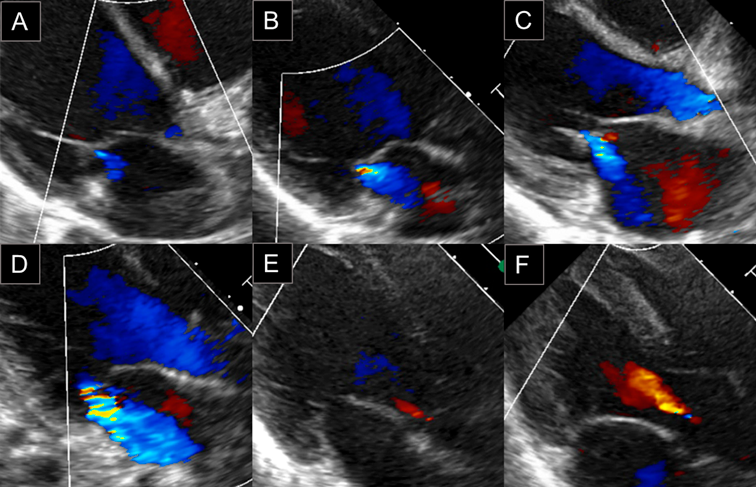

心エコー検査はPhilips EPIQ7を用い,全症例とも同一の小児循環器専門医の立ち会いのもと計測を行った.冠動脈の評価についてはZ score projectによるCoronary Z score Calculator Version 4.0を用い7),seg1, seg5, seg6, seg11のうちZが最大のものをZ maxとした.弁逆流の評価については,カラードプラをアーチファクトが出ない最大表示とした上で計測を行い,房室弁逆流では弁下部に限局し便宜上流速が計測できないものをtrace(Fig. 2A, 2B),カラーシグナルが心房後壁に達しないものをmild(Fig. 2C),カラーシグナルが心房後壁に達ししたものをmoderate(Fig. 2D),心房心室容量負荷がみられるものをsevereと定義した.肺動脈弁閉鎖不全(PR, pulmonary regurgitation)については,弁下部に限局しているものをtrace, traceとmoderateの間をmild,左右肺動脈で逆流が明らかのものをmoderate,右室容量負荷がみられるものをsevereと定義した.ARについては,弁下部に限局しているものをtrace(Fig. 2E),カラーシグナルが僧帽弁前尖を超えないものをmild(Fig. 2F),カラーシグナルが僧帽弁前尖を超えるものをmoderate,左房左室容量負荷がみられるものをsevereと定義した.三尖弁閉鎖不全(TR, tricuspid regurgitation),PRは通常でもtrace程度はみられることが多いため,経過中にmild以上となり退院約1か月後の外来で軽減したものを変化あり(+)とし,MR, ARは通常はみられないことが多いことから入院中にtrace以上で出現し退院1か月後の外来受診時に消失が確認できたものを変化あり(+)とした.PEは,水平断面,左室短軸断面,左室長軸断面の3方向で心臓全体をスキャンし,左室自由壁,右室自由壁の臓側心膜および壁側心膜の間に拡張期に1 mm以上で測定可能,もしくは心尖部に5 mm以上で測定可能な液貯留を認める場合に変化あり(+)とした.LVEFの算出には,左室短軸断面で計測した拡張末期径,収縮末期径を用いた.

Fig. 2 Classification of valvular regurgitation

(A) MR trace, (B) MR trace, (C) MR mild, (D) MR moderate, (E) AR trace, (F) AR mild AR, aortic regurgitation; MR, mitral regurgitation